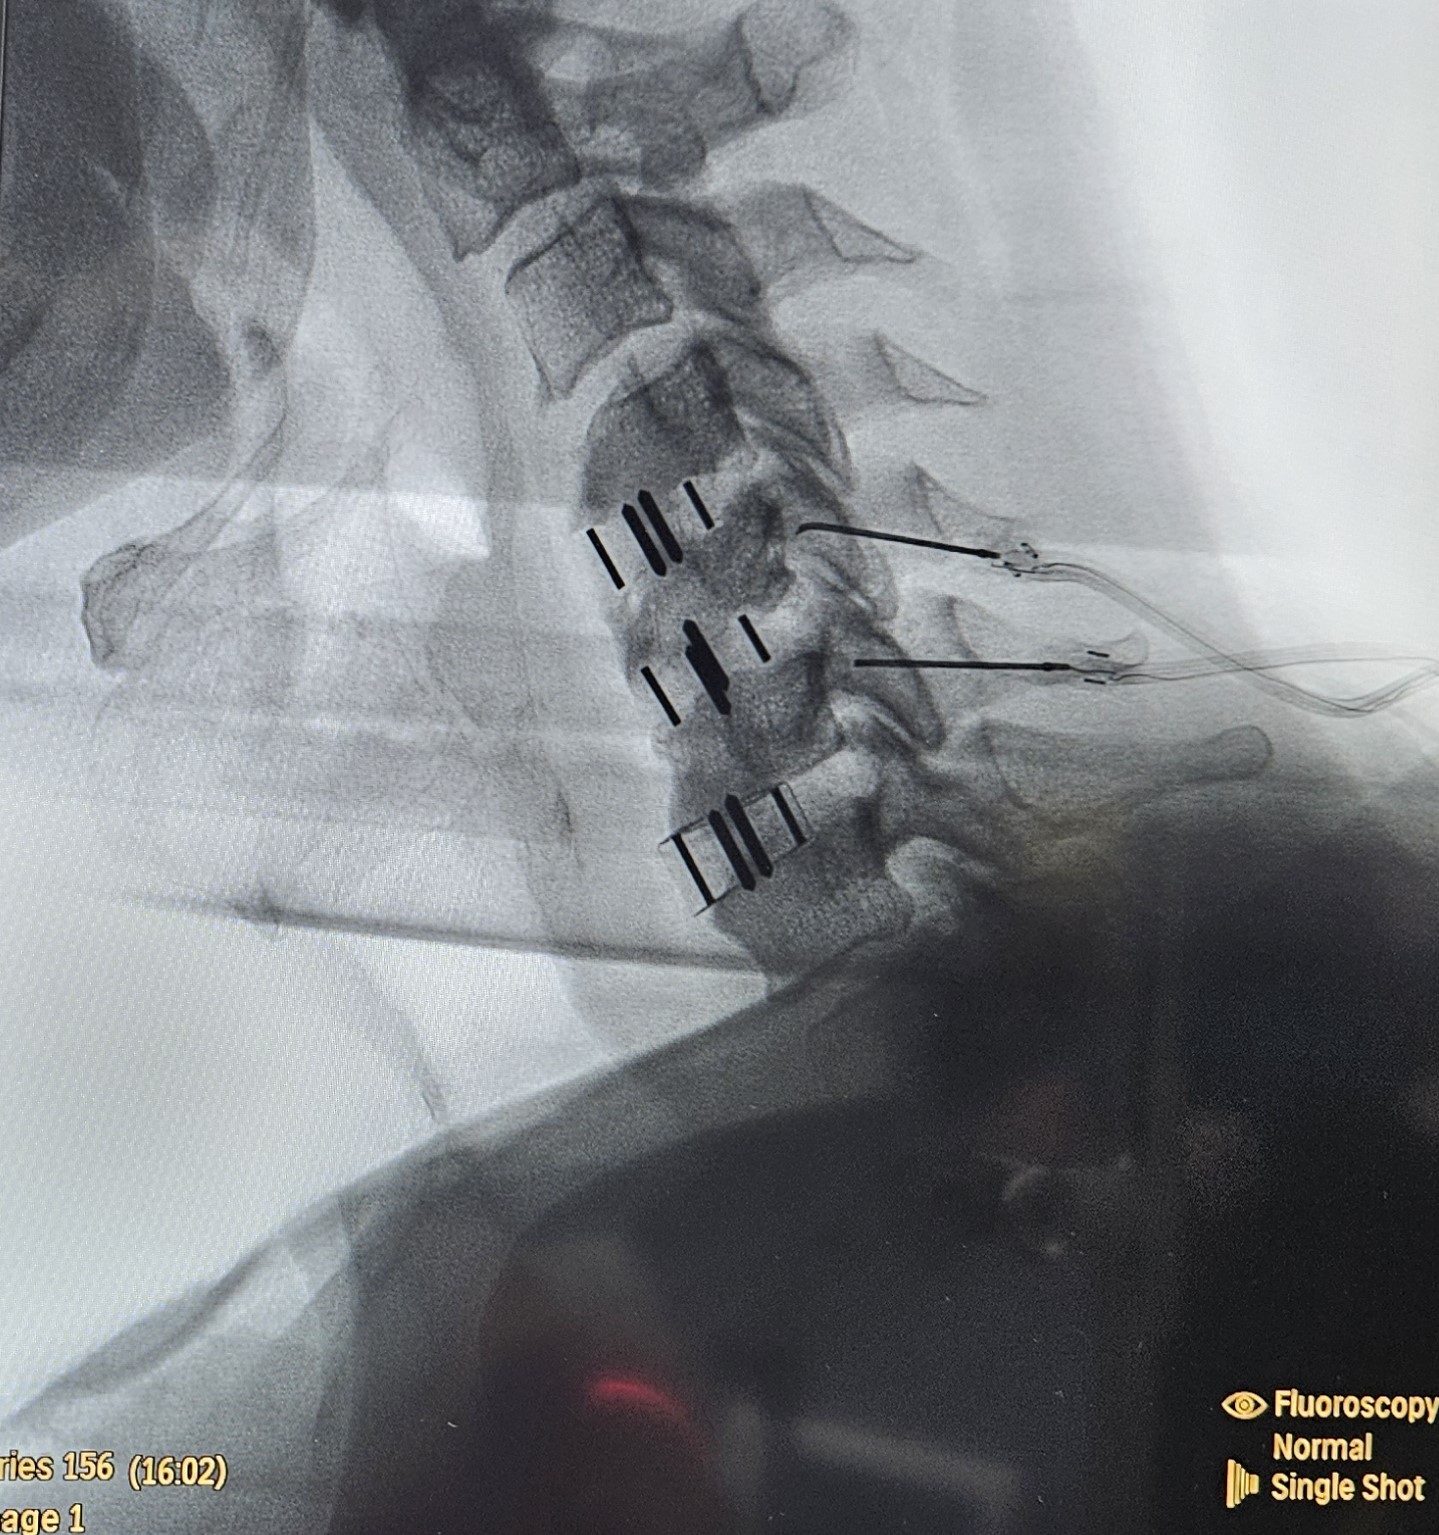

• Ενδοαρθρική έγχυση ή διαγνωστικός φαρμακευτικός νευρικός αποκλεισμός της άρθρωσης  προς επιβεβαίωση της πηγής του πόνου. Εάν υπάρξει άμεση ανακούφιση από τον πόνο, τότε η άρθρωση είναι πιθανώς η αιτία.

• Ενδοαρθρικές εγχύσεις κορτικοστεροειδούς υπό ακτινοσκοπικό έλεγχο

• Φαρμακευτικός νευρικός αποκλεισμός των μέσων νευρικών κλάδων που μεταφέρουν τα μηνύματα πόνου από την άρθρωση. Γίνεται με τη βοήθεια υπερήχου ή ακτινοσκοπικού

• Κατάλυση των μέσων νευρικών κλάδων με χρήση ραδιοσυχνοτήτων υπό ακτινοσκοπική καθοδήγηση

Με τον ασθενή σε πρηνή ή πλάγια κατακεκλιμένη θέση, χορηγείται τοπική αναισθησία για να μουδιάσει το δέρμα. Ο ιατρός εισάγει μια λεπτή βελόνα στο σημείο εντοπισμού των μέσων νευρικών κλάδων κάτω από ακτινοσκοπική καθοδήγηση. Ακολουθεί κινητικός και αισθητικός ερεθισμός και επί κατάλληλων ενδείξεων, η βελόνα συνδέεται με την πηγή ενέργειας, αφού εγχυθεί μικρή ποσότητα αναισθητικής ουσίας, για να μην δυσφορεί ο ασθενής κατά τη διάρκεια της παρέμβασης. Η ίδια διαδικασία ακολουθείται σε όλα τα επίπεδα που χρήζουν κατάλυσης.